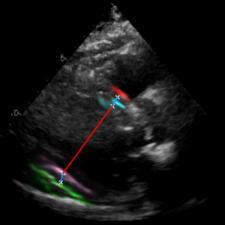

Left Ventricular Hypertrophy (LVH), one of the leading predictors of adverse cardiovascular outcomes, is the condition where heart’s mass abnormally increases secondary to anatomical changes in the Left Ventricle (LV) [10]. These anatomical changes include an increase in the septal and LV wall thickness, and the enlargement of the LV chamber. More specifically, Inter-Ventricular Septal (IVS), LV Posterior Wall (LVPW) and LV Internal Diameter (LVID) are assessed to investigate LVH and the risk of heart failure [21]. As shown in Figure 1 (a), four landmarks on a parasternal long axis (PLAX) echo frame can characterize IVS, LVPW and LVID, and allow cardiac function assessment. To automate this, machine learning-based (ML) landmark detection methods have gained traction.

It is difficult for such ML models to achieve high accuracy due to the sparsity of positive training signals (four or six) pertaining to the correct pixel locations. In an attempt to address this, previous works use 2D Gaussian distributions to smooth the ground truth landmarks of the LV [9, 13, 18]. However, as shown in Figure 1 (b), for LV landmark detection where landmarks are located at the wall boundaries (as illustrated by the dashed line), we argue that an isotropic Gaussian label smoothing approach confuses the model by being agnostic to the structural information of the echo frame and penalizing the model similarly whether the predictions are perpendicular or along the LV walls.